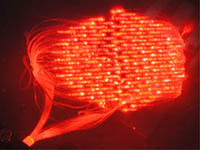

Optical imaging sensor for brain

Tissue for tumor irradiation in photodynamic therapy